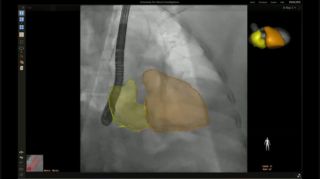

En el centro de nuestra suite, la exclusiva solución EchoNavigator es el ejemplo emblemático del compromiso de Philips con la multimodalidad y la integración del flujo de trabajo, aporta lo mejor de ambos mundos del líder de la industria en soluciones cardíacas intervencionistas de rayos X y ecografía.

Implementación de la superposición de la ETE 3D en vivo de la oclusión de la LAA con EchoNavigator

Guía de punción transeptal mediante EchoNavigator